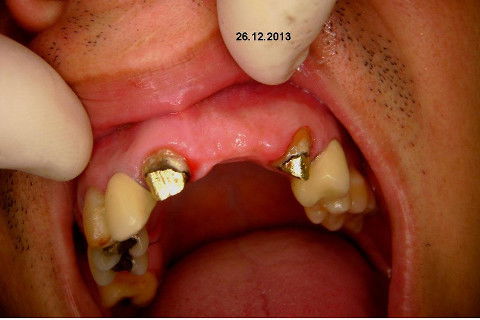

Paciente apareceu em meu consultório em dezembro/2013 para resolver problema de insatisfação com ponte fixa provisória anterior, realizada há 9 anos atrás (2004)...pretendia realizar somente a reabilitação em maxila/anterior, não contava com outros problemas com maior gravidade na sua boca, o máximo que citou foi a indicação para a exodontia do 16...

Fotos do caso